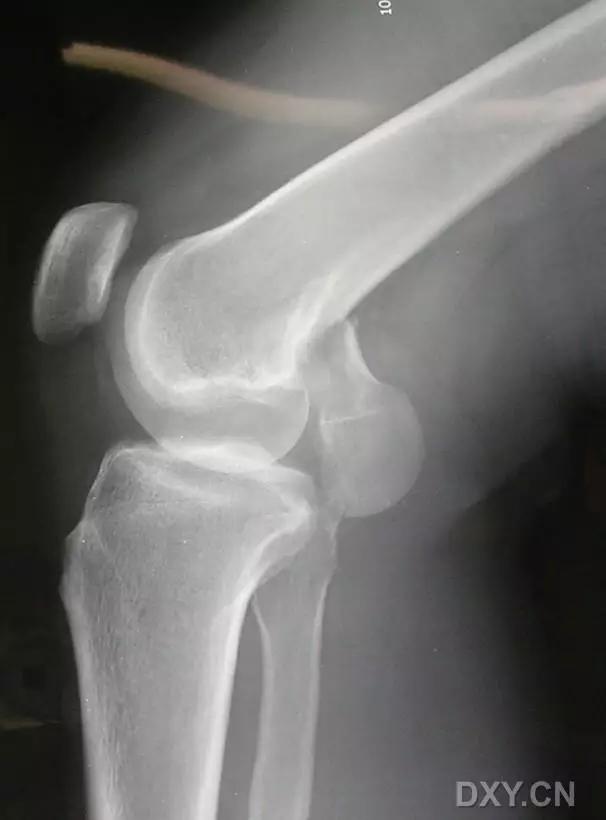

5. Hoffa 骨折

指股骨远端冠状面的骨折。

病例 1:一般股骨髁间、髁上粉碎骨折中含 Hoffa 骨折的不少见,但单纯后髁骨折则很少见。

正位片

侧位片

水平位 CT